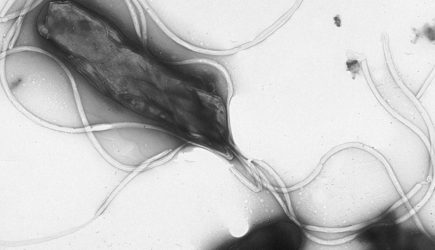

По словам врача, часто к раку желудка приводят воспаления слизистой оболочки этого органа. «Наиболее изученным фактором риска является инфекция Helicobacter pylori, которая может приводить к формированию атрофического гастрита, кишечной метаплазии и другим предраковым изменениям», — предупредил Бамматов.